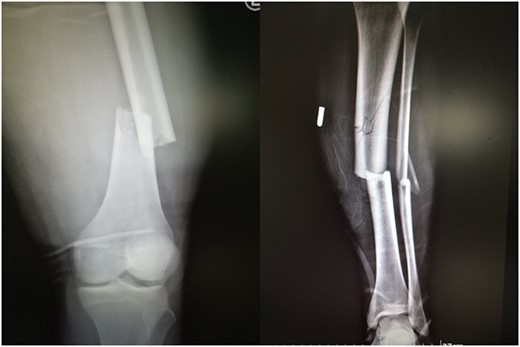

A 19-year-old male patient was admitted to the orthopedic department of our institution after a motorbike accident. The patient sustained a diaphyseal fracture of the left femur and ipsilateral tibia (floating knee) (Fig. 1), along with a right acromioclavicular joint type II injury and a right minimally displaced distal radius fracture. The patient was scheduled for emergent surgery. He underwent a retrograde intramedullary nailing of the left femur and an antegrade intramedullary nailing of the left tibia, under general anesthesia (Fig. 2). The operation was performed with the patient in the lithotomy position. The right intact leg was applied in 1000 of the hip flexion and 900 of the knee flexion. The duration of the surgery was 4 h and 20 min.

Ipsilateral femoral and tibial shaft fracture of the left limb (floating knee).